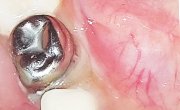

We deliver high-quality crowns with quick production times, helping you maintain efficiency in your practice without compromising on durability or aesthetics.

We use only the finest materials ensuring that every crown offers exceptional strength, wear resistance, and a natural appearance.